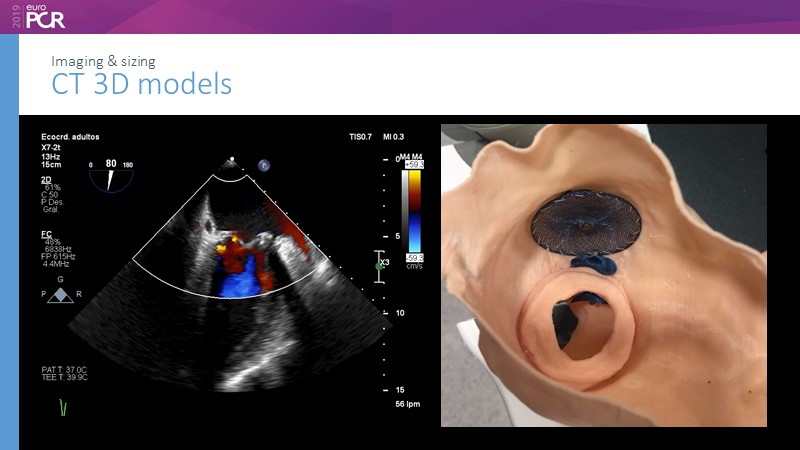

Pre-procedure planning

Previous Next